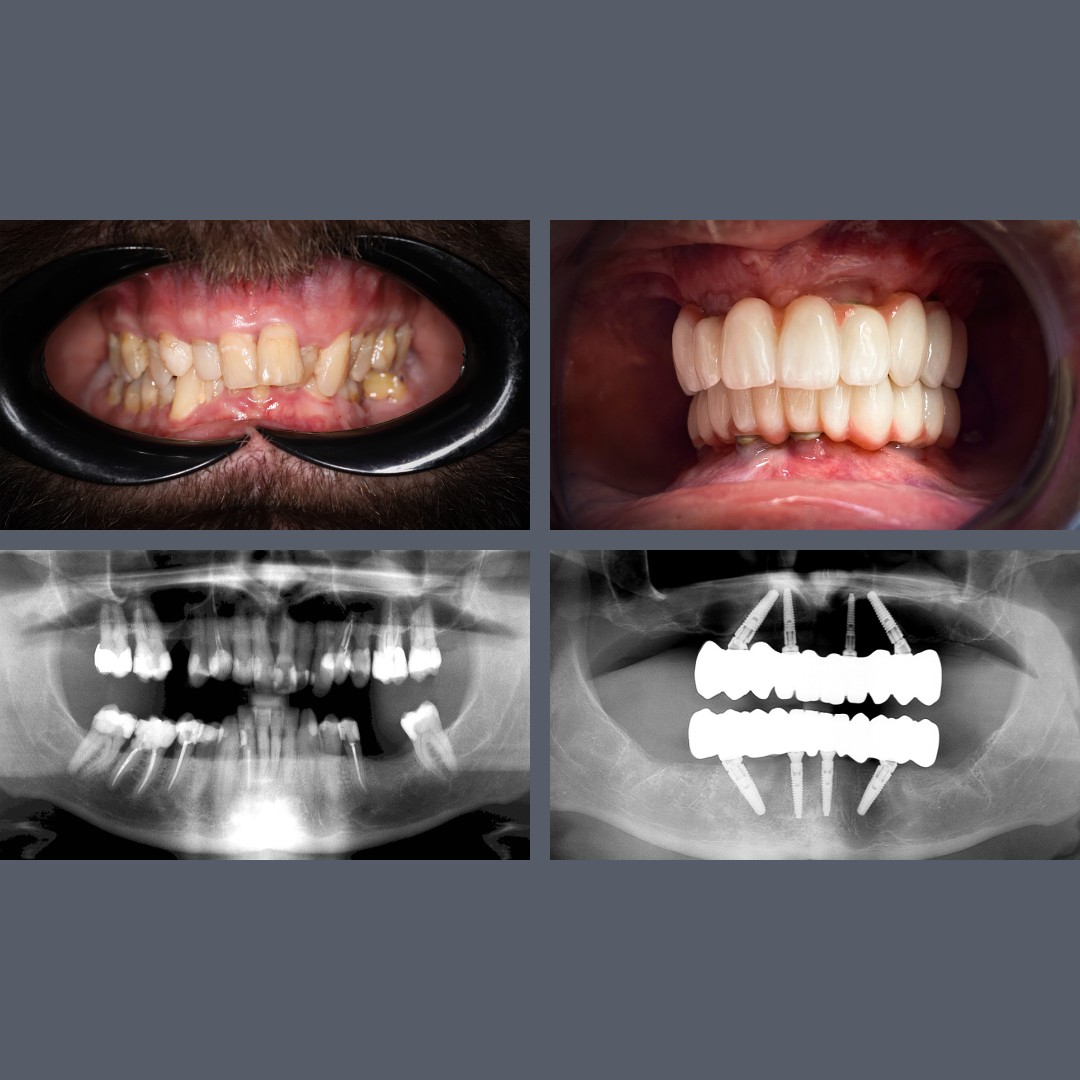

Gum Disease, Tooth Loss, Loose Teeth – All-on-4® Offers a Fixed, Long-Term Solution

Treatment: ALL-ON-4®